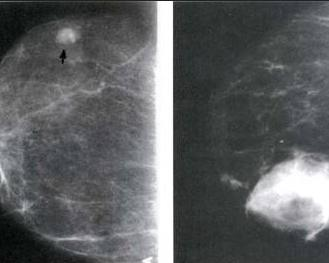

外伤性乳房血肿又称乳房外伤后血囊肿,主要是钝性外力作用于乳房引致的内局部血管断裂出血,进而形成局部的血性囊肿。临床上主要表现为乳房肿块,穿刺有血性液体为其特点。详细询问病史,对诊断有着重要意义。